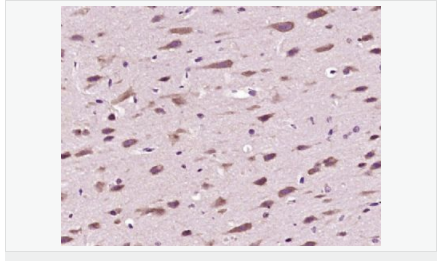

| 產(chǎn)品應(yīng)用 | ELISA=1:5000-10000 IHC-P=1:100-500 IHC-F=1:100-500 IF=1:100-500 (石蠟切片需做抗原修復(fù)) not yet tested in other applications. optimal dilutions/concentrations should be determined by the end user. |

| 細胞定位 | 細胞核 細胞漿 |

| 產(chǎn)品介紹 | The enzymes responsible for the reversible acetylation/ deacetylation process of histones are histone acetyltransferases (HATs) and histone deacetylases (HDACs), respectively. HATs act as transcriptional coactivators and HDACs are part of transcriptional corepressor complexes. Mammalian HDACs can be divided into three classes according to sequence homology. Class I consists of the yeast Rpd3 like proteins HDAC1, HDAC2, HDAC3, and HDAC8. Class II consists of the yeast Hda1 like proteins HDAC10, HDAC5, HDAC6, HDAC7, HDAC9, and HDAC10. Class III comprises the yeast Sir2 like proteins. Whereas class I HDACs are ubiquitously expressed, most class II HDACs are tissue specific. HDAC10 is similar to HDAC6, both containing a unique putative second catalytic domain not found in other HDACs. However, this domain is not functional in HDAC10. The deacetylase activity of class II HDACs is regulated by subcellular localization. HDAC10 was localized to both the nucleus and cytoplasm. HDAC10 can deacetylate histones, repress transcription, and interact with HDAC3. Function: Responsible for the deacetylation of lysine residues on the N-terminal part of the core histones (H2A, H2B, H3 and H4). Histone deacetylation gives a tag for epigenetic repression and plays an important role in transcriptional regulation, cell cycle progression and developmental events. Histone deacetylases act via the formation of large multiprotein complexes. Subunit: Interacts with HDAC2, HDAC3 and NCOR2. Subcellular Location: Cytoplasm. Nucleus. Note=Excluded from the nucleoli. Tissue Specificity: Ubiquitous. High expression in liver, spleen, pancreas and kidney. Similarity: Belongs to the histone deacetylase family. HD type 2 subfamily. SWISS: Q969S8 Gene ID: 83933 Database links: Entrez Gene: 83933 Human Entrez Gene: 170787 Mouse Omim: 608544 Human SwissProt: Q969S8 Human SwissProt: Q6P3E7 Mouse Unigene: 26593 Human Unigene: 203954 Mouse Unigene: 107028 Rat Important Note: This product as supplied is intended for research use only, not for use in human, therapeutic or diagnostic applications. |